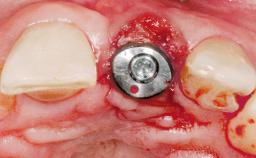

Immediate Flapless Placement of an Implant in a Maxillary Right Lateral Incisor Site

This 43-year-old male patient, a non-smoker, came to our practice because of a fracture of tooth 12 caused by a bicycle accident. Due to the combined para- and infrabony crown and root fracture, tooth extraction, and subsequent implant placement were suggested to the patient as the therapy of choice. The patient had high esthetic expectations with regard to the treatment outcome and asked for an immediate fixed provisional restoration. His individual esthetic risk profile summed up to a medium esthetic risk.

Type of Implants Two-Piece

Placement Protocol Immediate implant placement

Tooth Site Maxillary incisor or canine

Bone Volume Sufficient, with intact walls